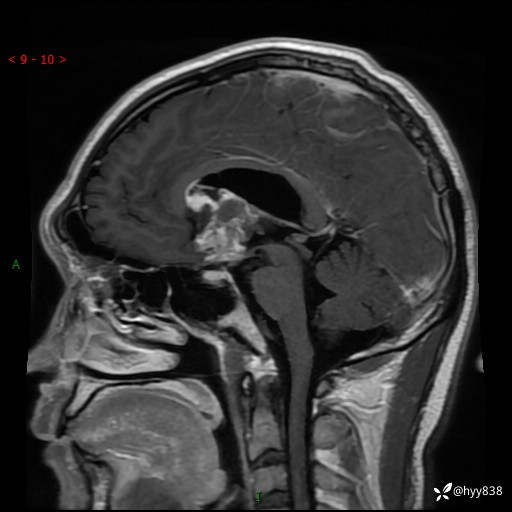

颅脑MRI平扫+增强